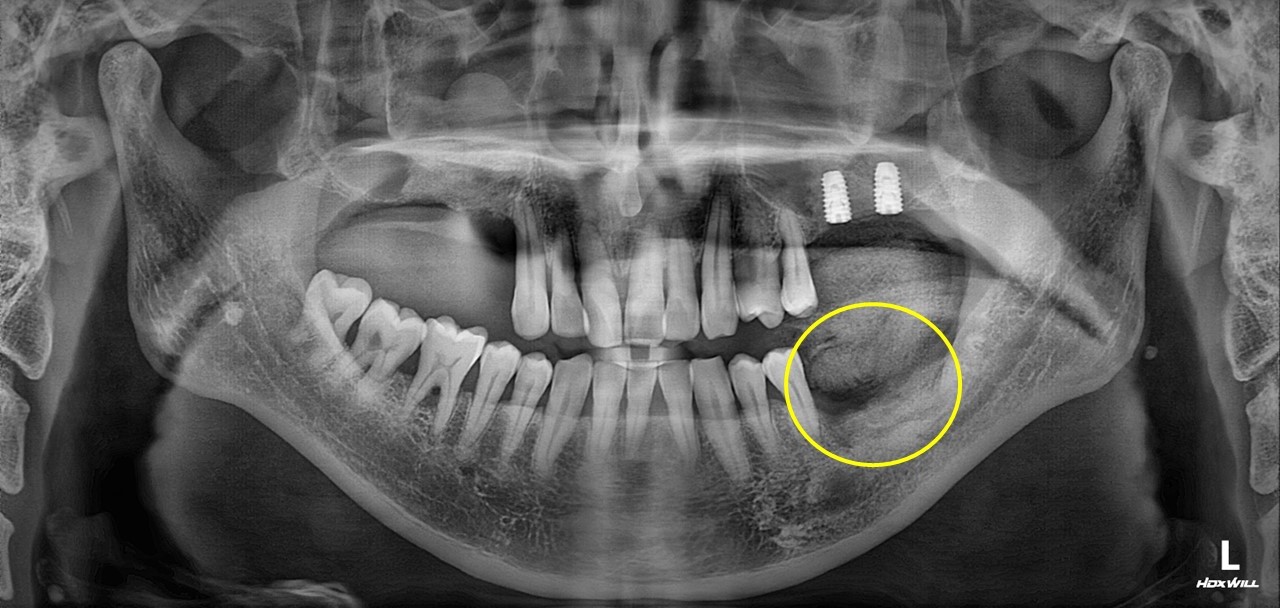

치조골 이식술 사례